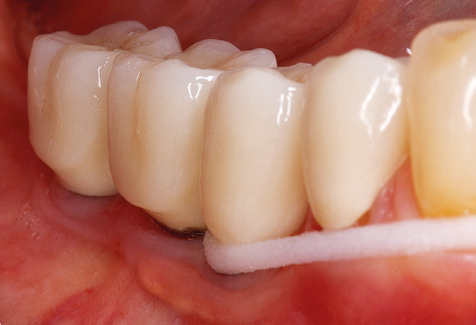

Fig. 9: The accessible implant and tooth surfaces are polished with polishing cups and suitable polishing compounds. – Fig. 10: Repeat instruction in the use of appropriate aids for oral hygiene at home should also form part of SPT. – Fig. 11a and b: Clinical situation 12 years after insertion of the prosthetic restoration. During this period, only a veneering ceramic fracture on tooth 47 and the requirement for endodontic treatment of tooth 12 were observed. All restorations are still functioning as intended.

Standardised and regular risk-adapted care in the scope of SPT is the key to treatment success for the clinical long-term success in periodontically compromised patients. This is particularly true for patients fitted with implants following successfully completed periodontal treatment (Fig. 11a and b).